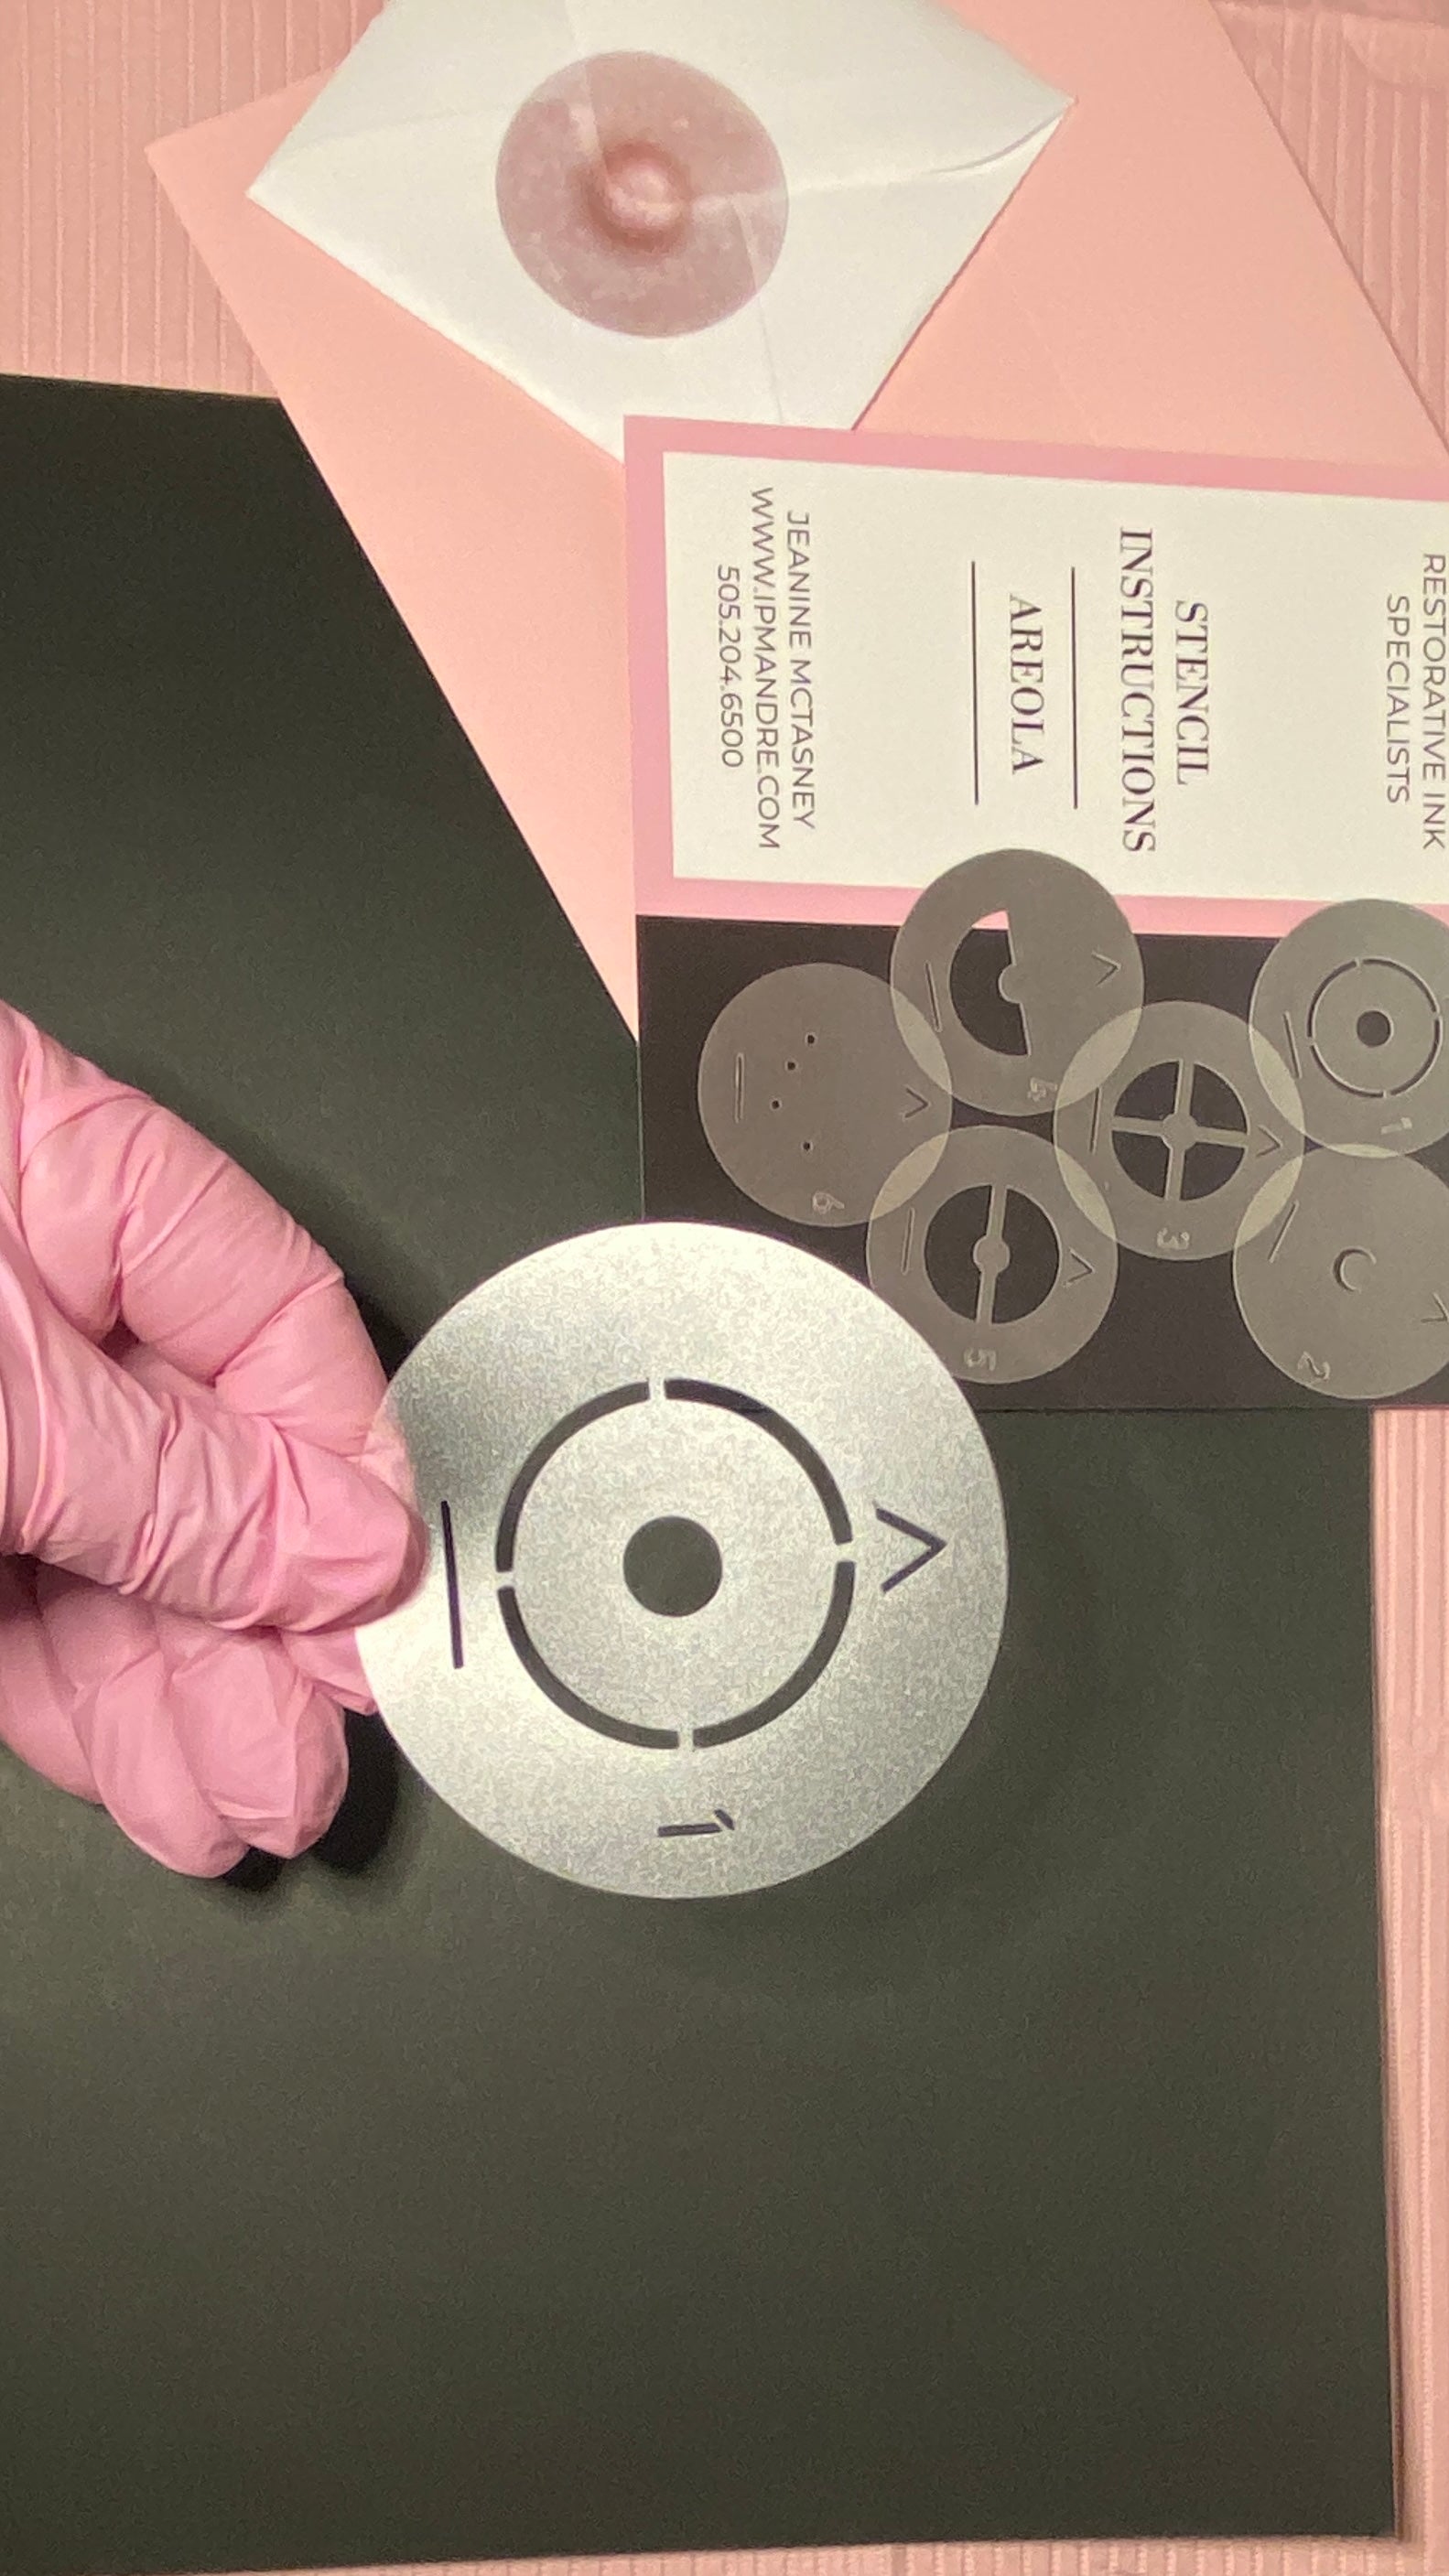

Creating a realistic, 3-D nipple/areola tattoo can be challenging — especially for new technicians learning the process. This 3-D Areola Tattoo Stencil Set is designed to simplify and guide you through each stage of areola restoration. With 6 professional-grade stencils and an 8-step workflow, you’ll have a clear visual roadmap while leaving space for your artistic interpretation and shading techniques to shine.

Made from 10mil polycarbonate film, these stencils are impact-resistant, clear, and durable — safe for practice pad work and even direct use during live procedures. They are steam autoclavable, alcohol-safe, and compatible with Sani-Cloth wipes, making them easy to clean and reuse safely. Ideal for PMU artists, medical tattooists, and professionals offering breast reconstruction finishing, scar camouflage, or restorative areola tattooing.